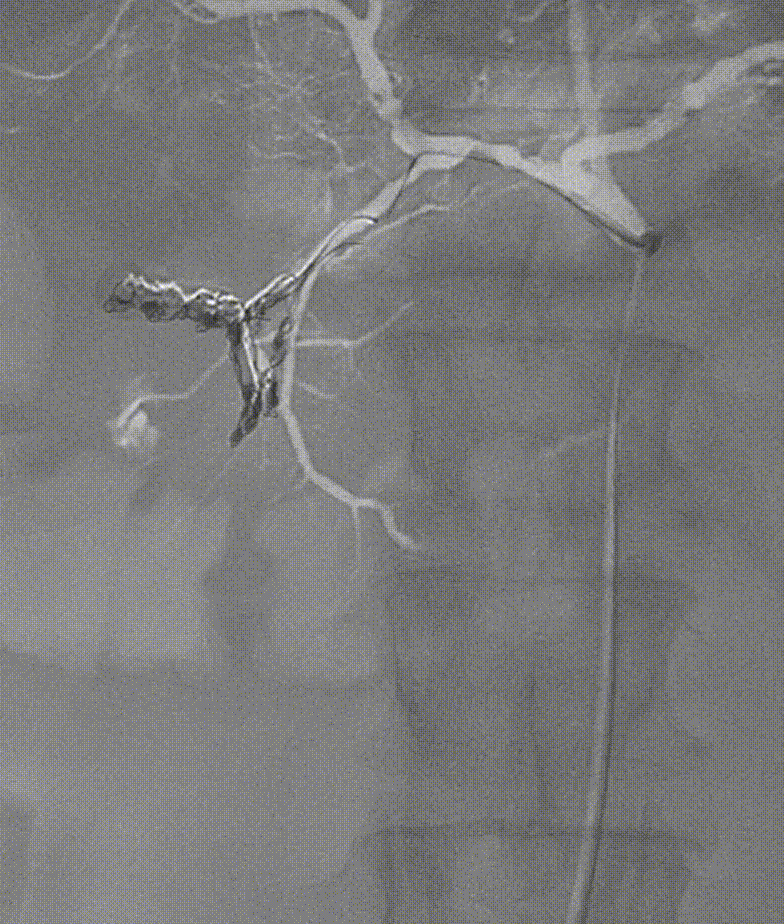

图:A:空肠动脉畸形;B回盲部肿瘤染色:CD:胃十二指肠动脉瘤